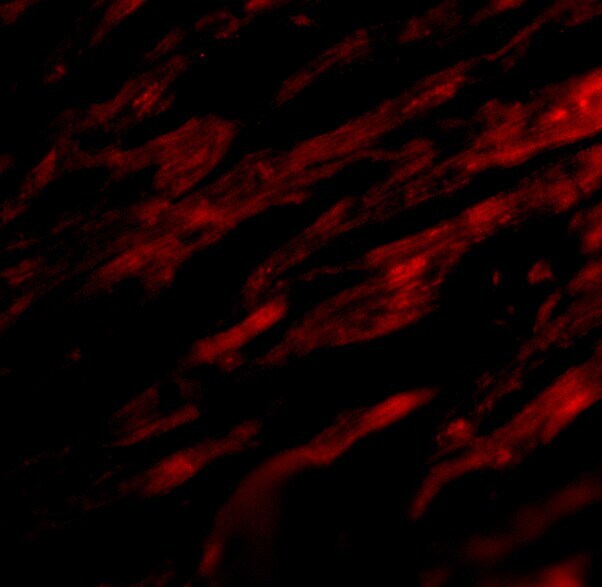

- Immunofluorescence analysis of 4% paraformaldehyde-fixed rat heart tissue labeling PD-L1 with PD-L1 Polyclonal Antibody (Product # PA5-20343) at 20 µg/mL, followed by goat anti-rabbit IgG secondary antibody at 1/250 dilution (red).